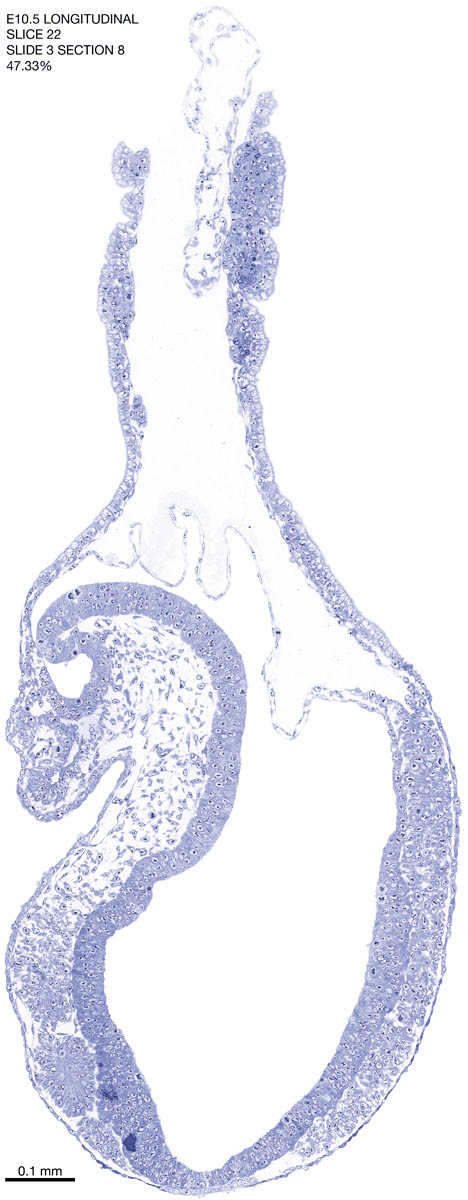

E10.5 Longitudianal Archive This page contains jpg files of ALL SLICES (each 3µm thick) that were scanned of the E10.5 longitudinally cut specimen. Download: Large | High Res Download: Large | High Res Download: Large | High Res Download: Large | High Res Download: Large | High Res Download: Large | High Res Download: Large | High Res Download: Large | High Res Download: Large | High Res Download: Large | High Res Download: Large | High Res Download: Large | High Res Download: Large | High Res Download: Large | High Res Download: Large | High Res Download: Large | High Res Download: Large | High Res Download: Large | High Res Download: Large | High Res Download: Large | High Res Download: Large | High Res Download: Large | High Res Download: Large | High Res Download: Large | High Res Download: Large | High Res Download: Large | High Res Download: Large | High Res Download: Large | High Res Download: Large | High Res Download: Large | High Res Download: Large | High Res Download: Large | High Res Download: Large | High Res Download: Large | High Res Download: Large | High Res Download: Large | High Res Download: Large | High Res Download: Large | High Res Download: Large | High Res Download: Large | High Res Download: Large | High Res Download: Large | High Res Download: Large | High Res Download: Large | High Res Download: Large | High Res Download: Large | High Res Download: Large | High Res Download: Large | High Res Download: Large | High Res Download: Large | High Res Download: Large | High Res Download: Large | High Res Download: Large | High Res Download: Large | High Res Download: Large | High Res Download: Large | High Res Download: Large | High Res Download: Large | High Res